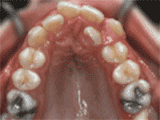

第四种

牙列拥挤,牙槽骨过窄,牙齿没有足够空间,只好前后左右高低上下乱长,经过矫正后的牙齿是这样的~